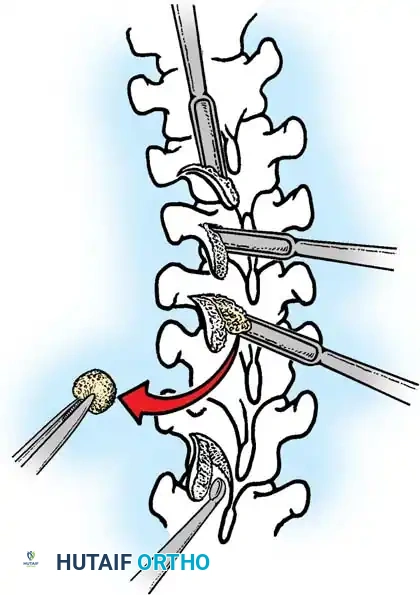

The Moe Technique (Thoracic Spine)

The Moe technique is a highly effective method for achieving intra-articular arthrodesis in the coronally oriented thoracic facet joints.

Fig. 38-26: The Moe technique of thoracic facet fusion, demonstrating the creation of hinged bone flaps.

- Expose the spine fully to the tips of the transverse processes.

- Using a sharp osteotome or Cobb gouge, begin a cut over the cephalad articular process at the base of the lamina.

- Carry this cut along the transverse process almost to its tip. Bend this cortical fragment laterally so it lies between the transverse processes, ideally leaving it hinged on its lateral periosteal attachment to preserve local vascularity.

- Thoroughly denude all articular cartilage from the superior articular process using a sharp curet.

- Make a secondary cut in the superior articular facet, working medially to laterally, producing another hinged fragment.

- Pack the resulting intra-articular defect tightly with cancellous bone graft.